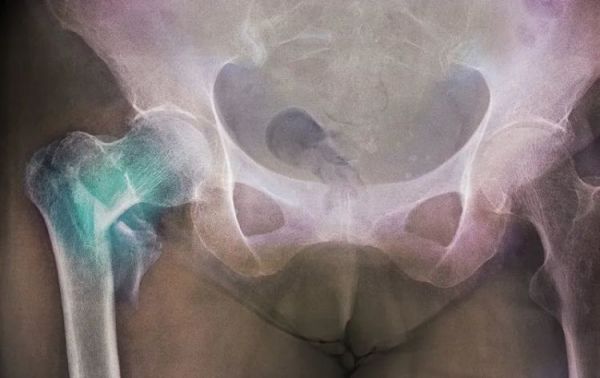

半月前不慎摔倒致右股骨颈骨折

无独有偶,李女士今年55岁,十年前进行了全胃切除术,此前不慎摔倒致左髋部骨折。通过检测和查体发现,李女士手臂肌力明显不足,下肢也较瘦弱,还伴有贫血的情况,营养筛查评分存在高危营养风险,评估为中-重度的营养不良。